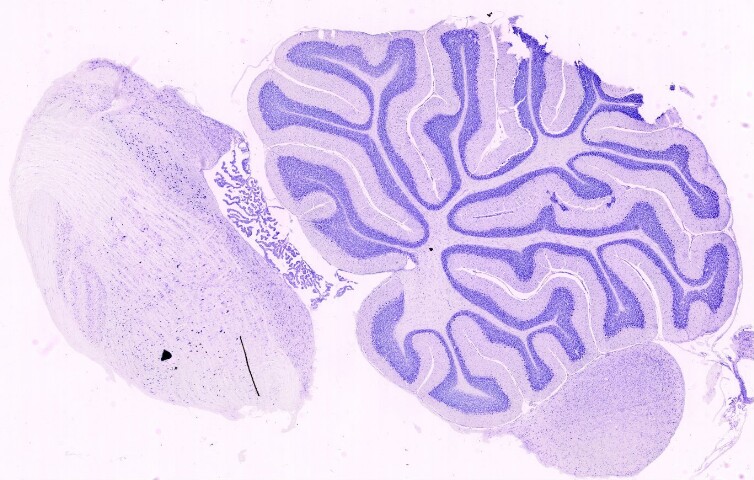

Cervelletto e tronco encefalico. Colorazione di Nissl

Sezione longitudinale del cervelletto e del tronco encefalico.